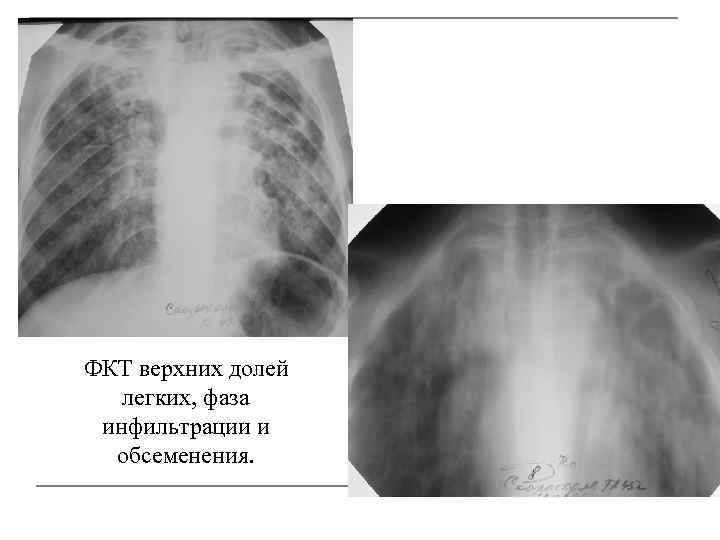

Иллюстрации по теме очагового и инфильтративного туберкулеза